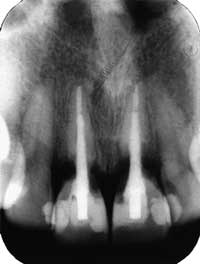

Cervikal rotresorpsjon er en betennelsesmediert ekstern resorpsjon av roten og kan være en bivirkning av intern bleking (7) (Fig. 2). I løpet av en tiårsperiode er det publisert 8 kasus med cervikal rotresorpsjon etter internbleking, og hvor tannen ikke hadde vært utsatt for traume (7). I en mindre oppfølgingsstudie av 58 internblekede tenner (30 % H202 og oppvarming) ble det funnet cervikal rotresorpsjon i 7 % av tennene (11), mens det i en tilsvarende studie med 112 tenner (NaBO3 oppslemmet i 30 % H2O2) ikke ble funnet slike skader (12). Typisk diagnostiseres resorpsjonen flere år etter at behandlingen er utført (11,13). Etiologien er noe uklar, men i mange tilfeller er det brukt høye konsentrasjoner med H2O2 og oppvarming i forbindelse med klinikkbleking (7,11). Det antas videre at blekemidlet kan ha penetrert dentinkanalene og trengt ut i periodontiet og startet en kjemisk betinget inflammasjon. En annen mulighet er at dentinets struktur endres slik at det blir betraktet som et fremmedlegeme med en etterfølgende immunologisk betinget betennelse (13). Fraktur av tannkronen er også observert etter internbleking (14), og kan skyldes en kombinasjon av vevstap ved rotbehandlingen og blekingens effekt på kalsiumnivået i emalje og dentin (15).

Fig. 2: Cervikal rotresorsjon i 11 og 21 diagnostisert 12 år etter internbleking. Tennene var rotbehandlet på grunn av omfattende karies. Ingen opplysninger om traume. To år etter rotbehandlingen var tennene misfarget, og det ble utført internbleking med natriumperborat og 3 % hydrogenperoksid. Da resultatet ikke var tilfredsstillende etter tre ukers behandling, ble det supplert med klinikkbleking med 35 % hydrogenperoksid og varme i to ganger 30 minutter med én ukes mellomrom..